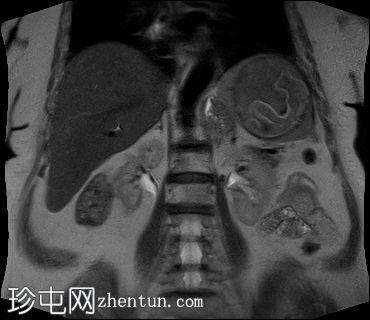

冠状位

T2加权像

脾脏内可见一边界清晰的病变,T2加权像呈中等信号强度,边缘低信号提示钙化。病变内可见漂浮膜,呈棘球蚴囊肿特征性的蛇形征。

本病例展示了一例脾脏棘球蚴囊肿,可见边缘及内部钙化。

蛇形征是棘球蚴(包虫)感染的特征性放射学表现。它指的是在复杂的包虫囊肿内观察到的离散的曲线状结构。这些结构代表内囊的层状膜从外囊壁脱落,形成囊内漂浮的膜状物,外观类似蛇。